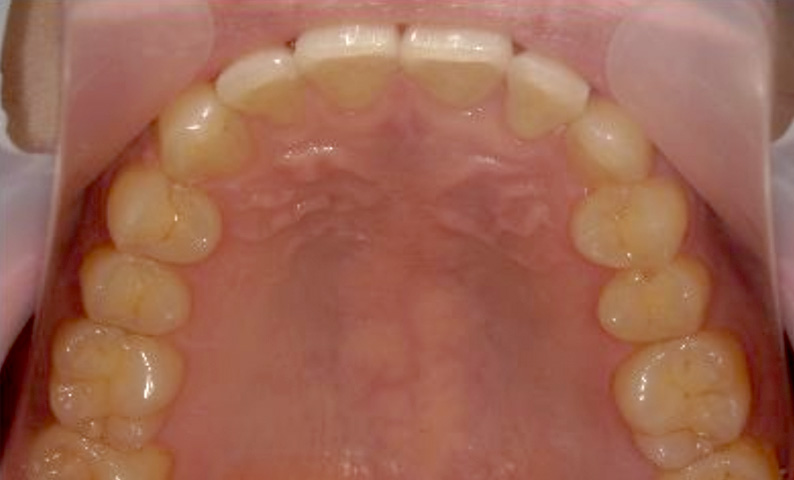

症例_002 上顎だけの部分矯正

治療期間:7ヶ月金額:30万円+税女性前歯のガタガタ上の前歯だけ

| Before | After |

|---|---|

|